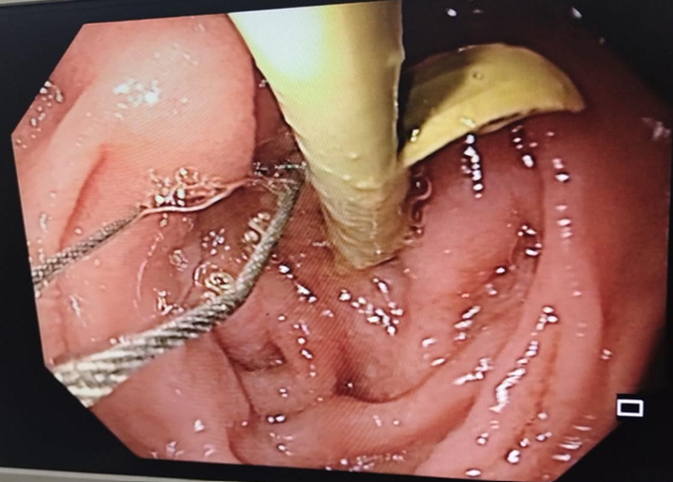

Figure 3. Illustration showing endoscopic retrograde cholangiopancreatography with common bile duct stent in-situ.

ERCP with sphincterotomy

In our study, ERCP with sphincterotomy was performed in 10 (16.6%) cases out of 60 patients. ERCP failed in 2 patients (3.3%). This corroborates with the findings of the study done by Vu et al. [27] that showed ERCP with stenting was done in 6 patients (21.4%) out of 28 patients.